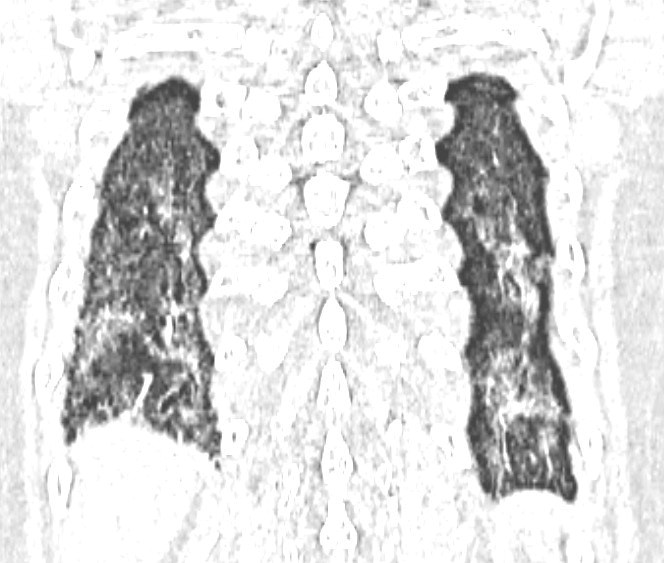

Kết quả xét nghiệm miễn dịch cho thấy sự hiện diện của nhiều tự kháng thể đặc hiệu. Chụp cắt lớp vi tính phổi phát hiện tổn thương phổi kẽ.

Từ các dữ kiện lâm sàng và cận lâm sàng, bệnh nhân được chẩn đoán mắc xơ cứng bì hệ thống thể giới hạn, kèm theo bệnh phổi kẽ và một số rối loạn liên quan đường tiêu hóa.

Không chỉ dừng lại ở da, xơ cứng bì hệ thống còn gây tổn thương nhiều cơ quan quan trọng. Ở phổi, bệnh có thể dẫn đến xơ hóa kẽ và tăng áp động mạch phổi. Ở tim, bệnh gây rối loạn nhịp hoặc suy tim. Hệ tiêu hóa có thể bị ảnh hưởng với biểu hiện khó nuốt, trào ngược. Trong khi đó, thận có nguy cơ xảy ra suy cấp – một biến chứng nguy hiểm, bác sĩ Hoài Nam cảnh báo.

Riêng với tổn thương phổi, cần kiểm tra chức năng hô hấp định kỳ, bao gồm các chỉ số thông khí như FVC, DLCO, đồng thời chụp CT phổi khi có dấu hiệu ho hoặc khó thở. Ngoài ra, việc tầm soát định kỳ các biến chứng tim mạch, thận và tiêu hóa cũng đóng vai trò quan trọng trong việc giảm nguy cơ tử vong.